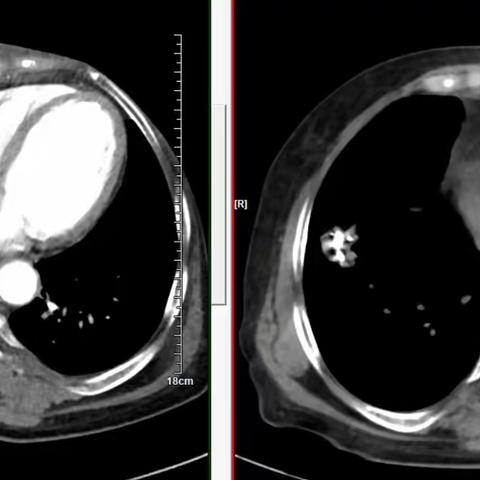

小粒子大作为——宜春市人民医院成功开展赣西首例肾上腺粒子植入术

精准爆破——碘125粒子对癌细胞的围剿